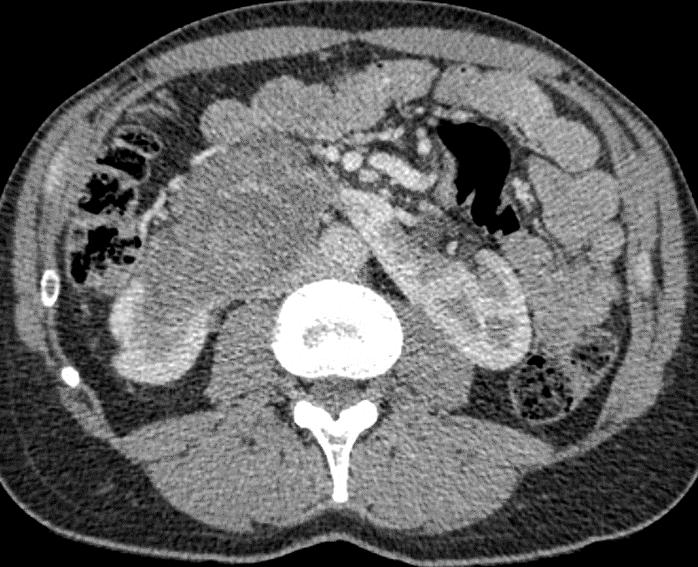

Obr. 1. Perioperační CT snímek během MWA.

Fig. 1. Perioperative CT scan during microwave ablation.

Výkon byl prováděn mikrovlnným systémem Solero Microwave Tissue Ablation System (AngioDynamics, Inc., USA). Během ablačních výkonů byla používána frekvence 2,45 GHz a výkon v rozsahu 100–140 W. Jako aplikátor byla používána nerezová ocelová jehla s keramickým hrotem o průměru 15 G a délce 14, 19 nebo 29 cm. Jedna ablační sekvence po zavedení jehly do tumoru trvá 4–6 min podle velikosti nádoru, v průběhu jednoho výkonu jsou standardně prováděny 1–2 ablační sekvence. Maximální velikost ablační zóny udávaná výrobcem je 54 × 39 mm na jednu sekvenci. Po skončení ablace tumoru se během vytahování jehly provádí ablace-koagulace punkčního kanálu (track ablace). Výkon je prováděn v analgosedaci za přítomnosti anesteziologa, pacienti snášejí výkon dobře. Celková doba výkonu vč. polohování pacienta a přípravy CT pracoviště je 60–90 min (obr. 1).